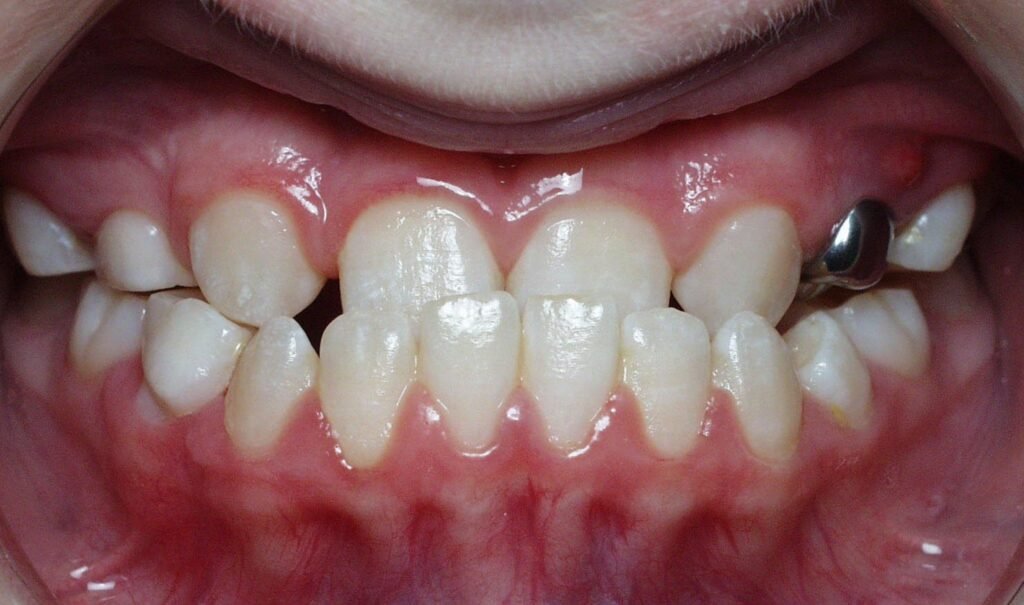

Crossbite

Clinical Presentation: One or more teeth bite on the inside of the opposing teeth.

Zebris Findings: Lateral discrepancies in jaw movement, uneven load distribution, and compensatory asymmetrical movements.